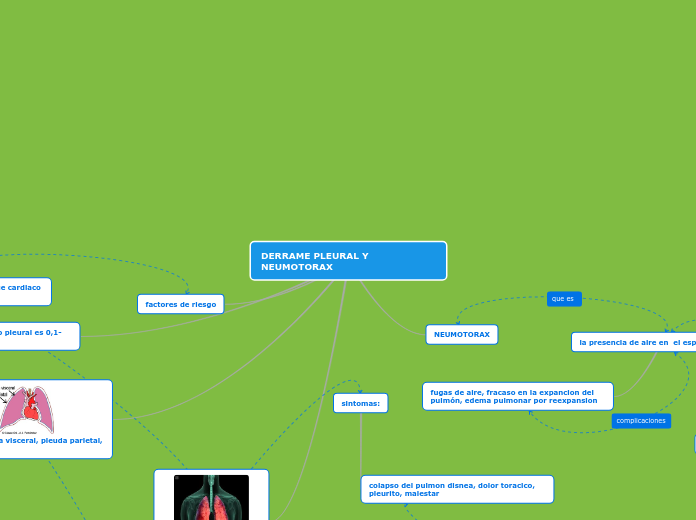

DERRAME PLEURAL Y NEUMOTORAX

el valor normal del liquido pleural es 0,1-0,2ml/kg de peso

ANATOMIA: pleura visceral, pleuda parietal, liquido pleural.

consiste en la acumulacion de liquido en el espacio pleural.

colapso del pulmon disnea, dolor toracico, pleurito, malestar

drenaje inadecuado,absceso, daño pulmonar,infecion,neumotoraxengrosamiento pleural.

la presencia de aire en el espacio pleural

fugas de aire, fracaso en la expancion del pulmón, edema pulmonar por reexpansion

colapso pulmonar parcial o completo

enfermedades pulmonares, ataque cardiaco artritis radioterapia